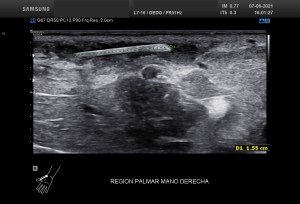

Recuerdo la importancia de comprobar siempre la permeabilidad de los vasos del hueco poplíteo con este tipo de patologías, el parecido de los síntomas de un quiste de Baker roto y la TVP puede ser muy similar y sin embargo, la TVP es una patología potencialmente peligrosa. Para ello pide al paciente que suba la pierna afectada por encima de su otra pierna para poder hacer que el retorno venoso sea más evidente y poder estudiar los mencionados vasos, sobre todo, su vena, claro.

La compresión con la sonda del hueco poplíteo establece la permeabilidad de la vena poplitea. Normalidad por tanto, manda, el comportamiento de la vena, compresible, y no el uso del doppler, por eso me permito el lujo de enseñarte la técnica sin el uso del doppler color. Línea roja: Si la vena no se colapsa.